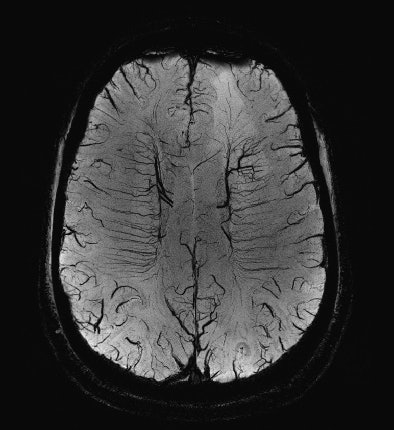

| A susceptibility-weighted image (SWI) with high spatial resolution illustrating the very small normal veins in the white matter of the brain. Note that on the left a malignant brain tumor is visible as a hyperintense lesion in the background. |

Besides the clinical field, whole-body systems up to 9.4 tesla have become available in experimental settings and have already proven to be significantly beneficial in special purpose examinations. Professor Fritz Schick, head of the department of experimental radiology in Tübingen, Germany, gives some examples: "One interesting field is highly resolved anatomical MRI of the brain or joints. Some contrast mechanisms are clearly more effective at higher field strength. Susceptibility-based imaging (SWI, BOLD, or T2*-imaging) significantly benefits from the ultrahigh field (7.0 tesla). Recent research has shown that functional MRI at 7.0 tesla provided better results compared to 3.0 tesla in the presurgical evaluation of patients with tumors located close to the senso-motor area in the brain. In patients with multiple sclerosis, susceptibility-weighted imaging (SWI) at 7.0 tesla reveals vein density and focal iron accumulations in MS plaques, which gives insight into the pathophysiology of this disease in vivo for the first time."